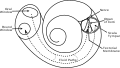

Vue de la paroi interne du tympan. La fenêtre du vestibule est l'ovale situé en haut. La cochlée.

La cochlée.